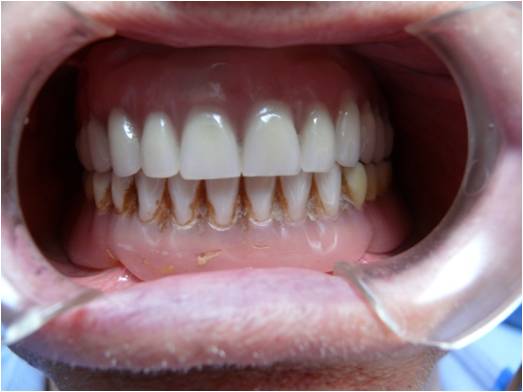

Chirurgia Oro-Mascellare per riabilitazioni protesiche post oncologiche

I pazienti che per motivi oncologici o per esito di osteonecrosi per uso di farmaci della categoria bifosfonati (in uso nelle gravi forme di osteoporosi o nel trattamento coadiuvante delle metastasi ossee)hanno subito gravi demolizioni dei mascellari e conseguente perdita della funzionalità masticatoria necessitano di ricostruzione e rifunzionalizzazione dell'apparato masticatorio con ricostruzione dell'osso mandibolare o del mascellare superiore attraverso innesti di osso , di lembi mucosi e/o muscolari di vicinanza ed a volte di implantologia preprotesica con impianti zigomatici , pterigoidei o convenzionali , tutto cio'con il fine di ripristinare una corretta funzione ma anche una auspicabile vita di relazione.

![]() | ![]() | ![]() | ![]() |